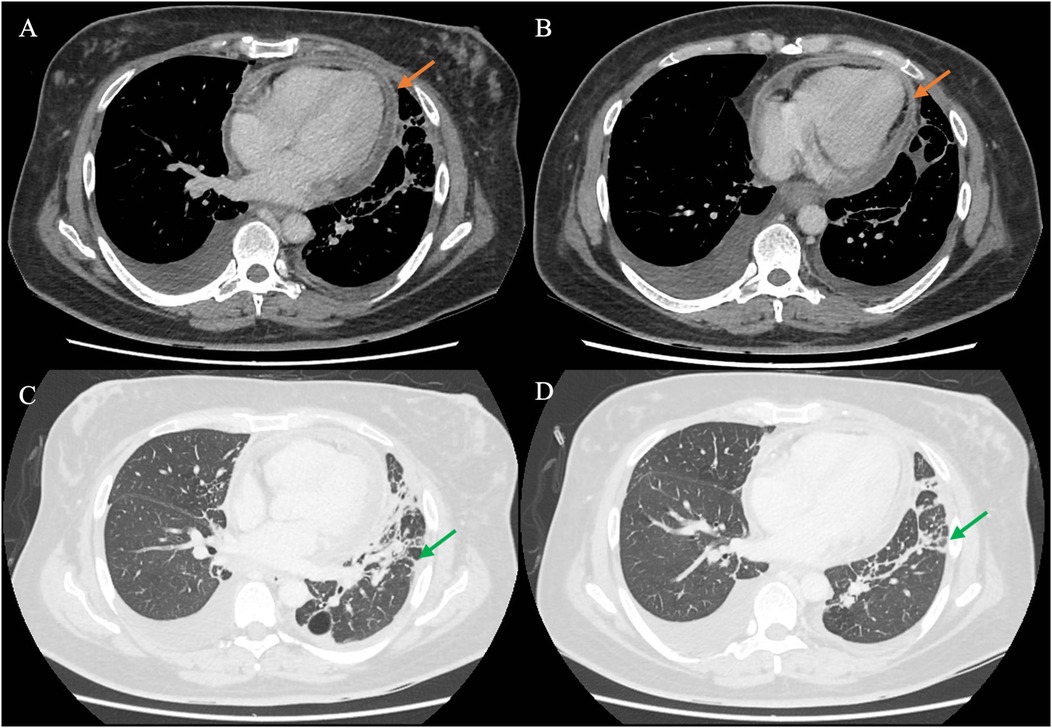

As the patient’s high fever did not abate on IV piperacillin/tazobactam, contrast-enhanced computed tomography (CT) of the thorax, abdomen, and pelvis was performed, revealing patchy consolidation in both lung lobes with air bronchograms in the right upper lobe and lingula segment (Supplementary Figure S2) and areas of bronchiectasis, scarring, and mediastinal lymphadenopathy that was stable compared to a previous examination conducted several years ago. These findings were consistent with post-tuberculosis lung disease. There were small bilateral pleural effusions. In addition, CT indicated an enhanced pericardial effusion 1.4 cm in size, consistent with pericarditis (Figure 1). The Department of Infectious Diseases was consulted, who recommended initiating IV meropenem, which treats the common etiologies of bacterial pericarditis and melioidosis, for which she was at risk due to her poorly controlled diabetes (Figure 2).

Figure 1. CT of the chest of the patient using different windows. (A,B) The chest CT in the soft tissue/mediastinal window, highlighting the pericardium (orange arrow) surrounding the heart. The findings are consistent with acute pericarditis with an associated pericardial effusion. (C,D) The lung window, in which streaky consolidation in the left lung is more clearly visualized (green arrow). CT, computed tomography.

CT provided additional insights, not only revealing pericardial enhancement (Figure 1) but additionally identifying small pleural effusions not evident on chest radiograph that provided an alternative target for obtaining diagnostic specimens. As S. aureus, a known cause of bacterial pericarditis, was detected in nucleic acid amplification testing of the pleural effusion, the suspicion for S. aureus pericarditis was heightened, prompting the decision to conduct a pericardial window and drain the pericardial fluid.